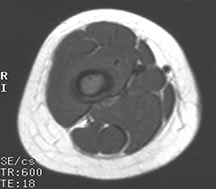

- May arise from any bone and any site within a bone (epiphyseal, metaphyseal, diaphyseal)

- Radiographically variable appearance: may appear benign (geographic) or malignant (permeative or moth eaten)

- Pain and soft tissue swelling

- Femur